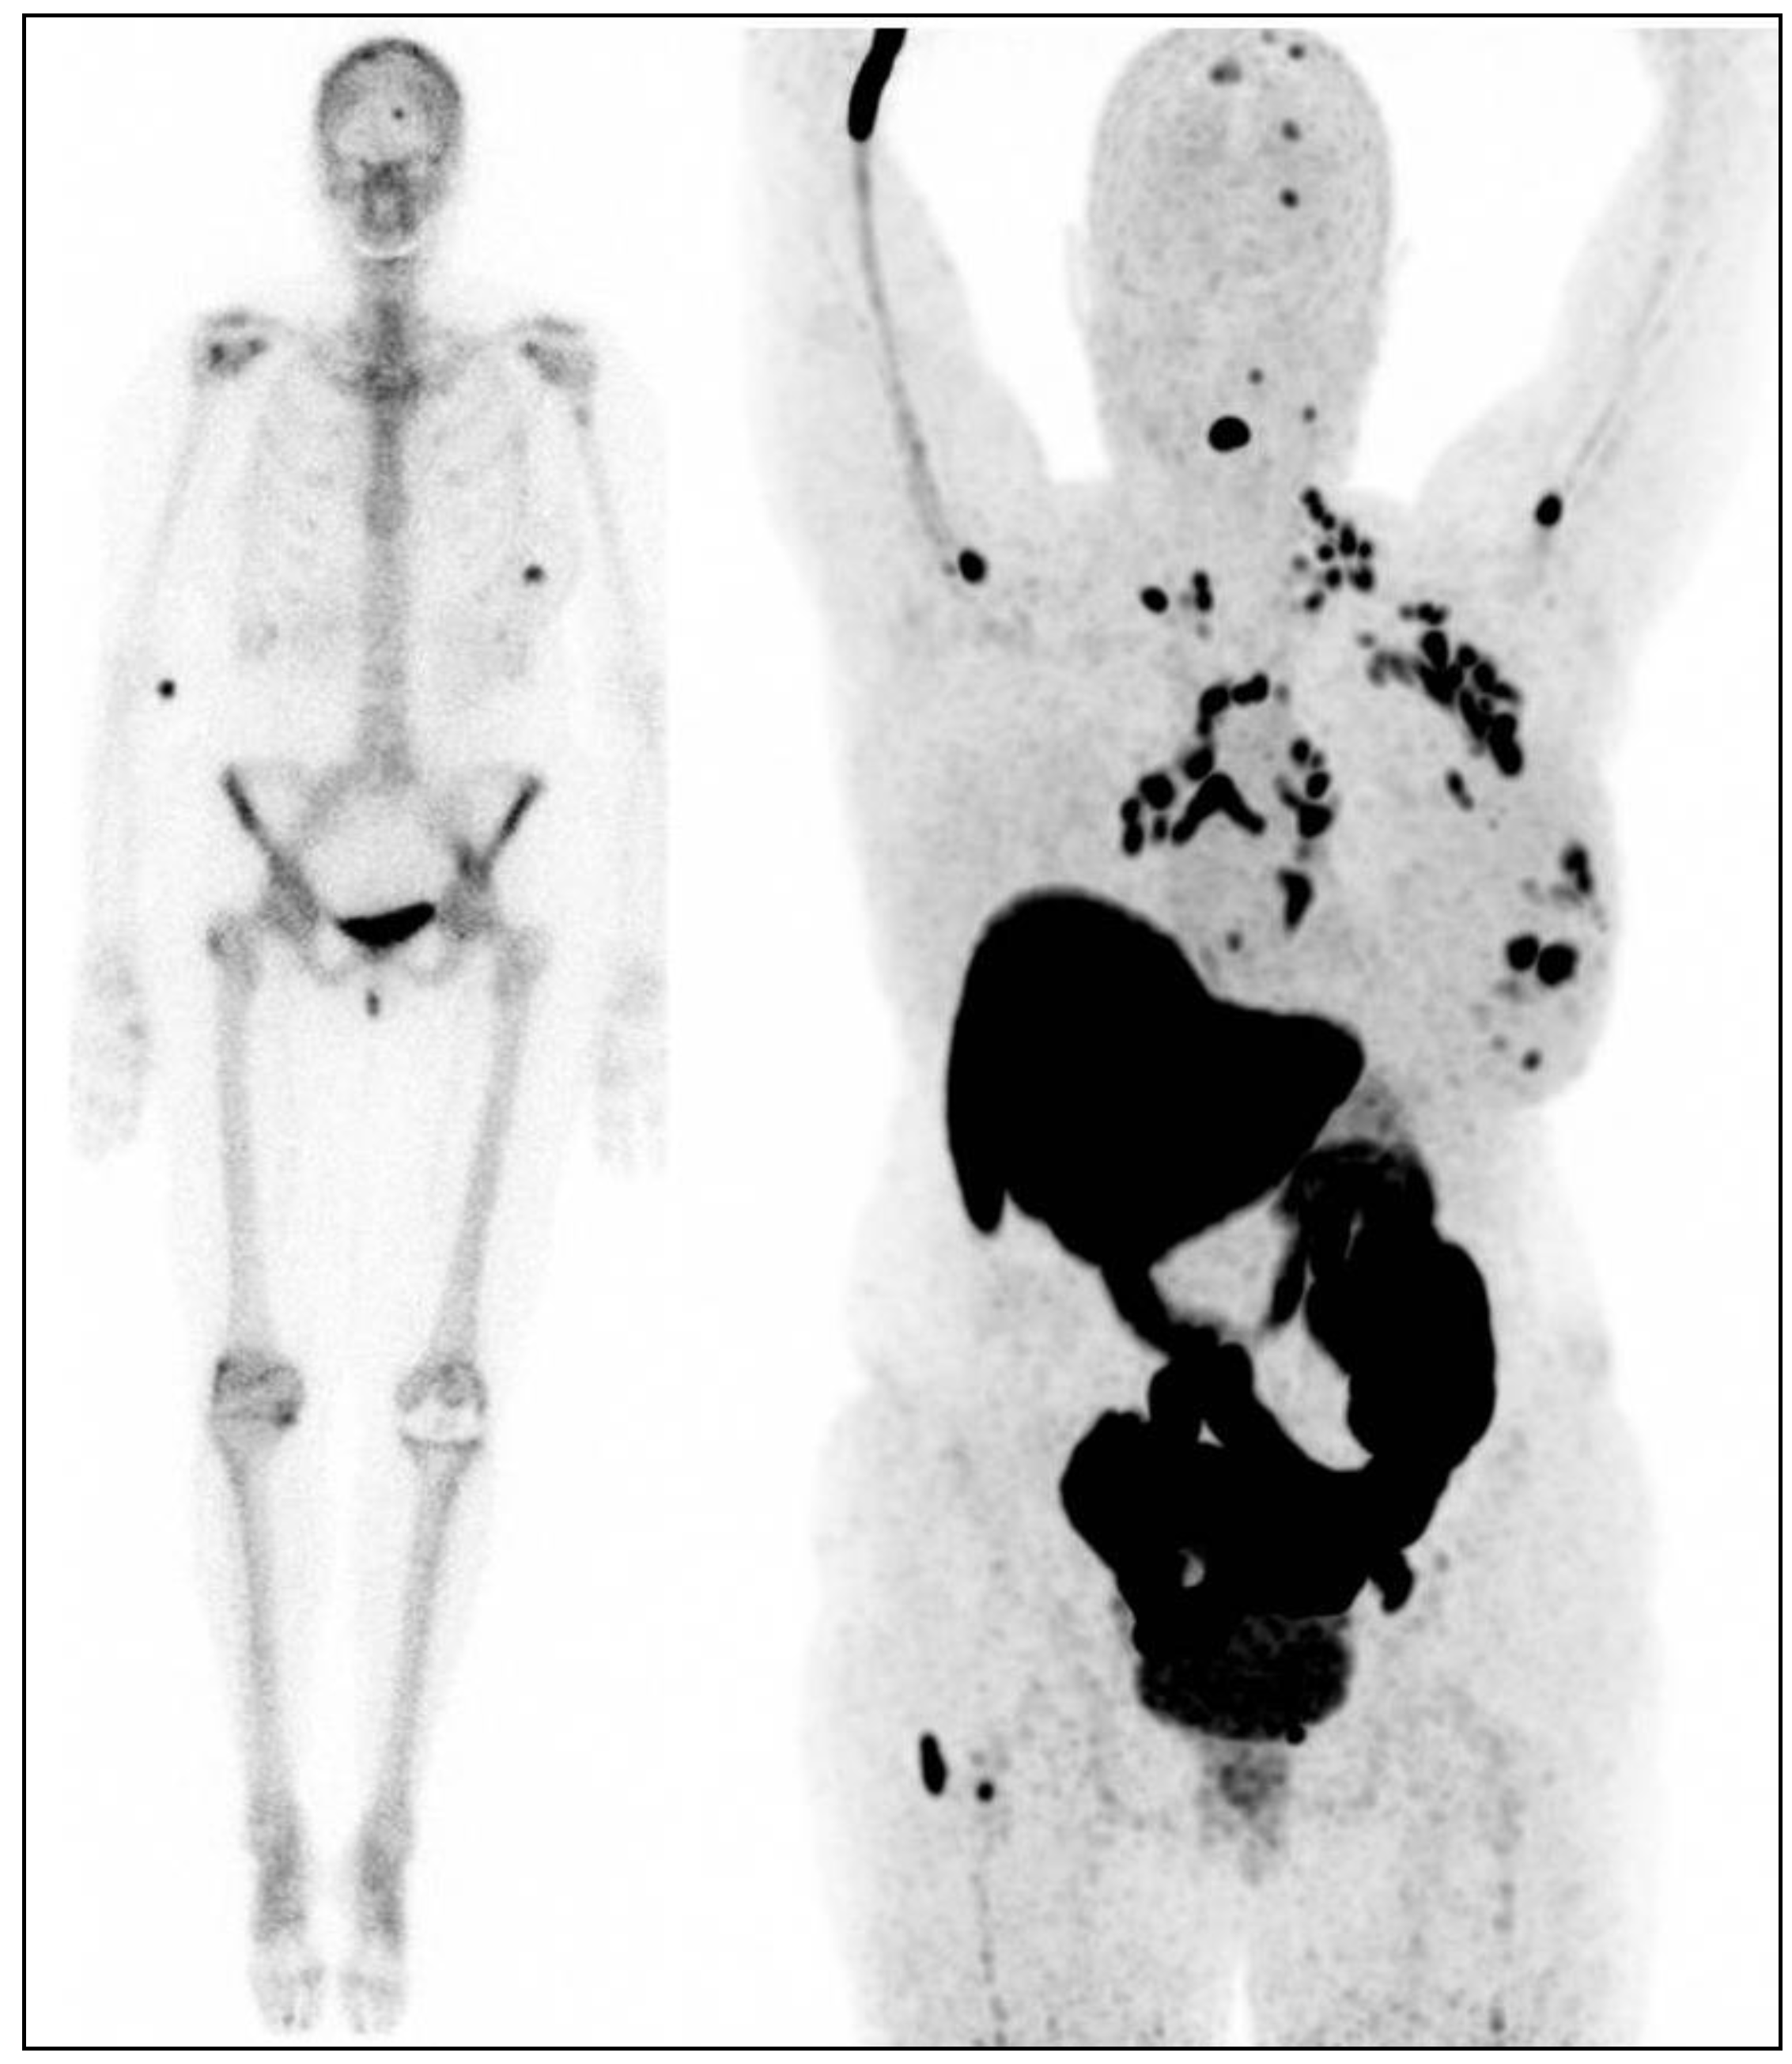

- Chan, D.L.H.; Pavlakis, N.; Schembri, G.P.; Bernard, E.J.; Hsiao, E.; Hayes, A.; Barnes, T.; Diakos, C.; Khasraw, M.; Samra, J.; et al. Dual Somatostatin Receptor/FDG PET/CT Imaging in Metastatic Neuroendocrine Tumours: Proposal for a Novel Grading Scheme with Prognostic Significance. Theranostics 2017, 7, 1149–1158. [Google Scholar] [CrossRef]

- Abdulrezzak, U.; Kurt, Y.K.; Kula, M.; Tutus, A. Combined imaging with 68Ga-DOTA-TATE and 18F-FDG PET/CT on the basis of volumetric parameters in neuroendocrine tumors. Nucl. Med. Commun. 2016, 37, 874–881. [Google Scholar] [CrossRef]